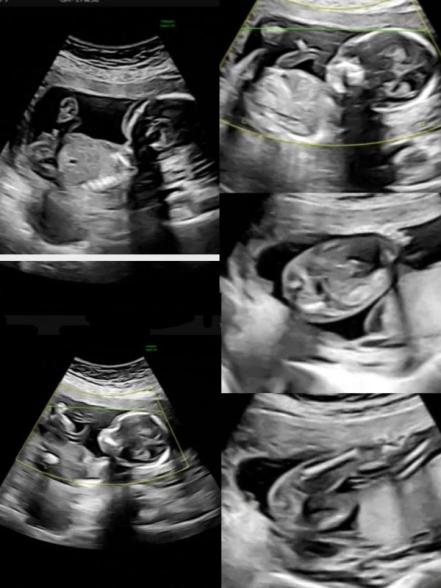

17週の時にエコーを取ってもらったのですが

どちら寄りに見えますか?

ついているようにも見えるけど臍の緒も見えるから

よく分からなくて‥個人的には男の子っぽいようには見えます

エコーのお写真を拝見いたしました。右側の一番下のものが、お尻を下の方から見ているような角度のものでしたね。

足を閉じているような状況でもありましたらの判断は難しかったです。

どちらよりもとも言い難い様子でした。

右側の1番下のものと、その上のエコーも

お尻を下から見たエコーでした(^^)

左の1番上のエコーは横からの写真ですが、タマっぽいのと、その先に🐘ゾウさんが見えたので、もしかしたら〜?と思っていましたが、やっぱりどっちかと言われたら分からないですよね(^◇^;)笑

右側の真ん中もそうでしたね!

よくよくみると、男の子シンボルのようにも見えますね。

途切れておらず、つながりのあるような線にも見えますので、男の子の可能性はありそうに思いました。

断定はできないのですが、次の健診の際にご確認をよろしくお願いします。